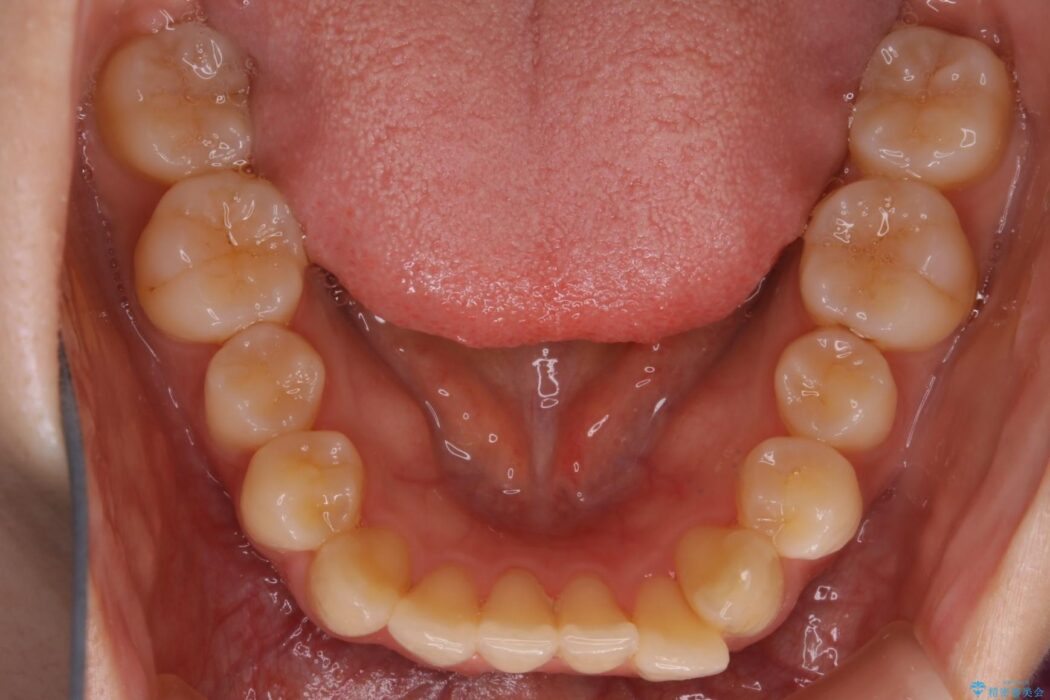

下の前歯のガタつきが気になるとご来院された患者様です。

インビザラインのライトパッケージにて、歯列拡大とディスキング(IPR)をを行いスペースをつくり非抜歯で治療を行いました。

歯並びが悪くなる原因の一つに「歯列弓の狭窄」というものがあります。

奥歯や前歯が内側(舌側)に倒れ込んでしまったり、歯が生えてくる位置が内側になってしまうことにより歯並びのアーチが狭くなってしまうことを言います。

このような場合、歯並びのアーチを拡大してあげるだけでもガタつきを無くすためのスペースがかなり作れることがあります。